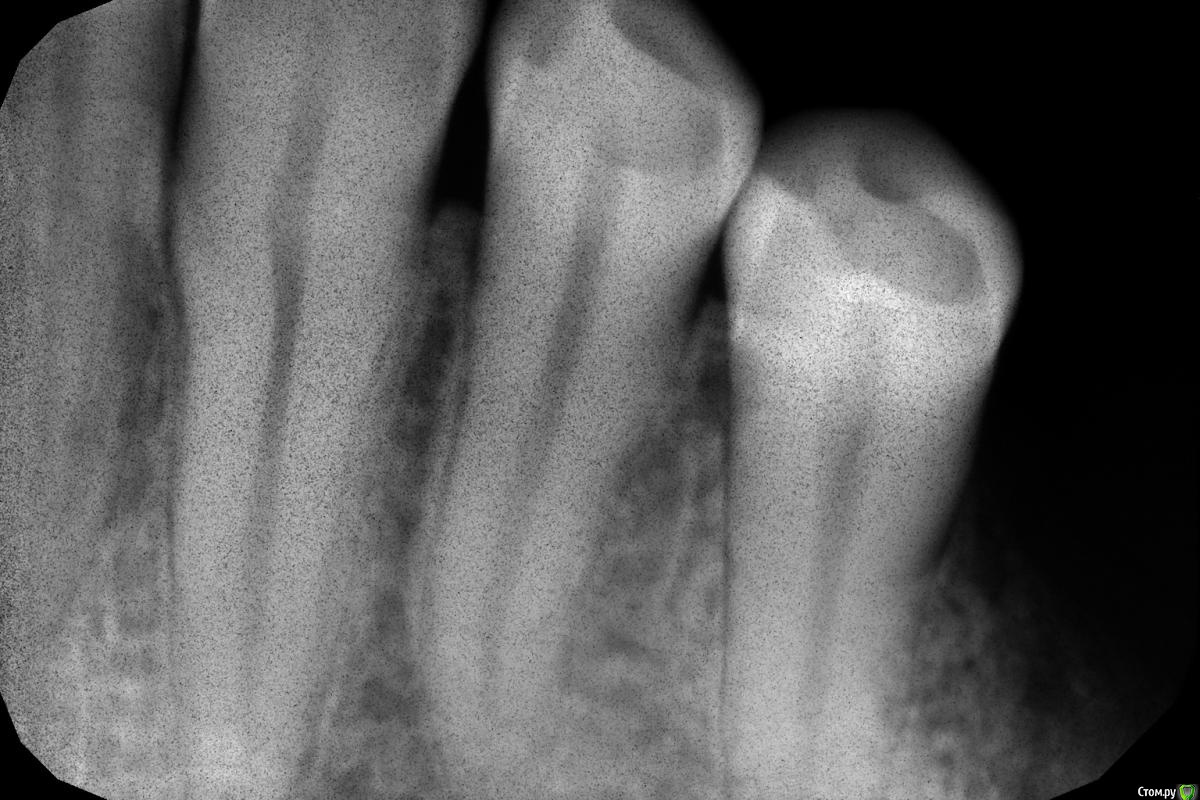

Xael Опубликовано 7 ноября, 2017 Автор Поделиться Опубликовано 7 ноября, 2017 (изменено) Добавляю рентген-фото больного зуба 3.4: Добавляю также фото больной(?) десны: Изменено 7 ноября, 2017 пользователем Xael Ссылка на комментарий

red_butler Опубликовано 7 ноября, 2017 Поделиться Опубликовано 7 ноября, 2017 снимок не информативен, верхушка корня не видна.Нужны термо проба хладагентом и/или ЭОД Ссылка на комментарий

Xael Опубликовано 7 ноября, 2017 Автор Поделиться Опубликовано 7 ноября, 2017 снимок не информативен, верхушка корня не видна.Нужны термо проба хладагентом и/или ЭОД Переделал снимок, термо и ЭОД только завтра возможны Ссылка на комментарий